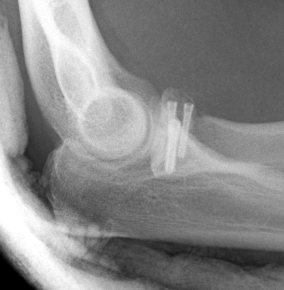

Complex Elbow Dislocation APComplex Elbow Dislocation Lateralelbo dis

terribleterribleterrible

Radial head replacement with lag screw fixation of Type II coronoid

terribleterribleterribleterrible

Radial head replacement with lasso fixation of small coronoid fragment